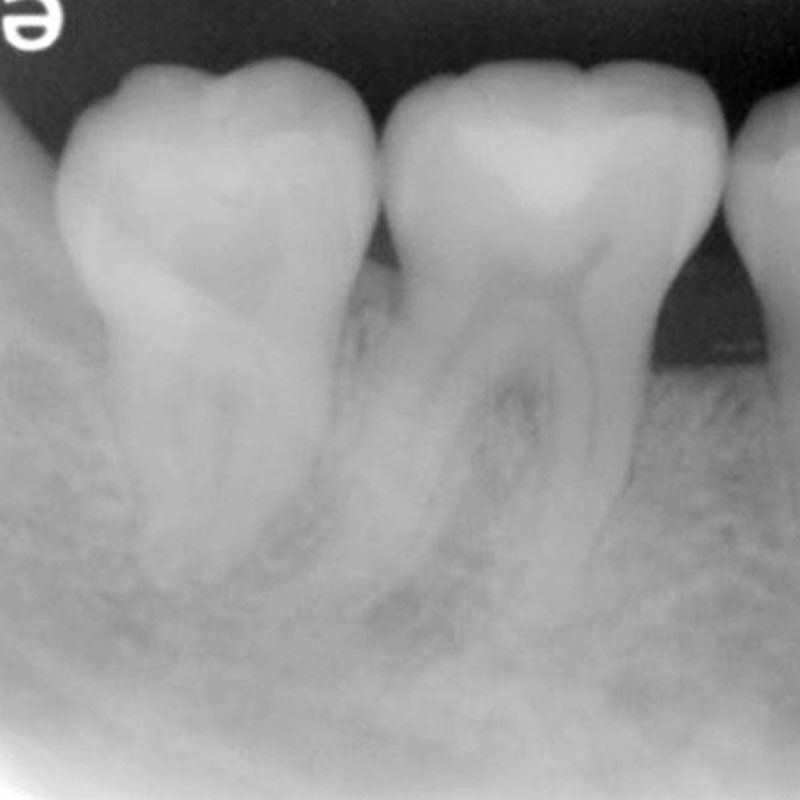

牙周再生手術

日期 : 106年7月11日